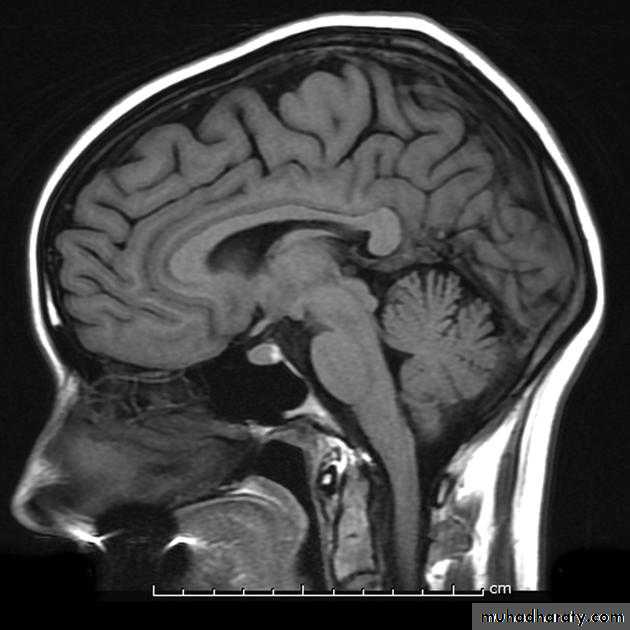

• 2. Medial surface:

• 1. Corpus callosum

• 2. The medial frontal gyrus

• 3. Cingulate sulcus & Cingulate gyrus

• 4. parieto-occipital sulcus

• Paracentral

• lobule

• Precuneus

• Cuneus

• Lingual

• 5. Calcrine sulcus